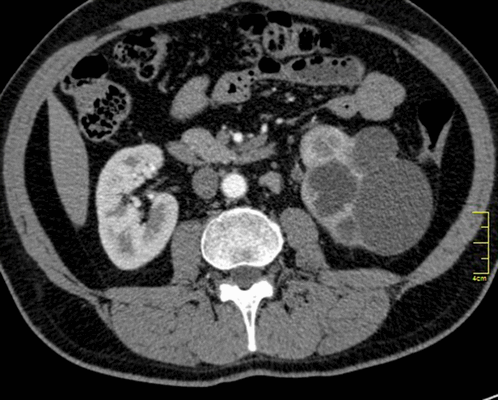

Палочка Коха, вызывающая туберкулез, может быть обнаружена в разных мягкотканных органах (печени, почках, мозге и др.) и костных структурах. Только при комплексной диагностике проводят дифференциацию патологии от других заболеваний, определяют степень, локализацию и тяжесть патологического процесса.

Туберкулез почки

- милиарный туберкулез характеризуется множественными очагами поражения (до 2 мм), локализованными во всех сегментах легких, часто обнаруживают патологии в печени, почках, кишечнике, селезенке, мозге, костях. Данный вид заболевания имеет неблагоприятный прогноз и высокую скорость прогрессии. Поэтому важна ранняя диагностика.

- проблемы с печенью или почками. Печень и почки помогают фильтровать отходы и примеси из кровотока. Туберкулез этих органов может нарушать их функции